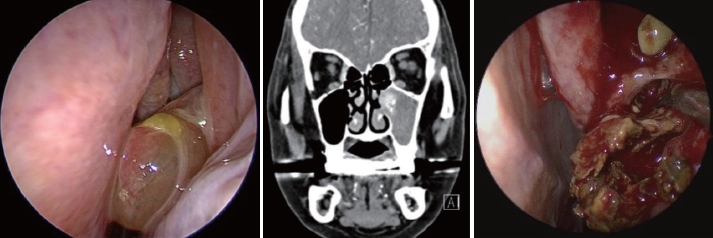

문 1. 79세 여자 환자가 좌측 비강 내 종물 소견으로 내원하였고, 이후 촬영한 CT 소견과 수술실 소견은 다음과 같다. 이 질환에 대해 옳은 것은?

① Alternaria가 주된 원인 균주이다.

② 진균에 대한 면역학적 반응이 주된 발병 기전이다.

③ 균사가 조직 내로 침범하는 침습성 형태의 부비동염이다.

④ 상악치아의 근관치료도 이 질환 발생과 관련이 있을 수 있다고 알려져 있다.

⑤ 국소 또는 전신 항진균제 투여가 필요하다.

문 1. 답 ④

해 설 진균구는 진균성 부비동염 중 발생빈도가 가장 높으나 양호한 경과를 보이는 질환으로 균사가 조직 내 침범없이 비부비강 내에 밀집 축척되어있는 상태이다. 면역기능이 정상인 경우가 대부분이며 항진균제 사용은 필요하지 않다. 상악치아의 근관치료와도 관련이 있는 것으로 알려져 있다.

참고 문헌: 대한이비인후과학회. 이비인후과학:비과. 개정2판. 파주: 군자출판사;2018. p.312-3.

Park GY, Kim HY, Min JY, Dhong HJ, Chung SK. Endodontic treatment: A significant risk factor for the development of maxillary fungal ball. Clin Exp Otorhinolaryngol 2010;3(3):136-40.